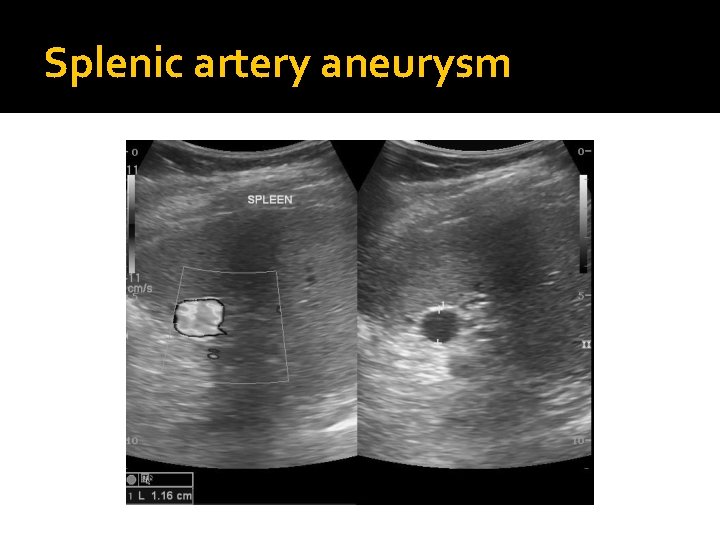

Splenic artery aneurysm �Typically, a calcified circle is seen in the left upper quadrant on an x-ray and a splenic artery aneurysm is suspected. �Sonographically, a splenic artery aneurysm may appear as a cystic mass, or if calcified, a hyperechoic shadowing foci in the area of the splenic artery. The artery should be traced from the celiac axis along the anterior aspect of the pancreatic tail to the splenic hilum. Filling the stomach with water may aid in visualizing the pancreatic tail.

Splenic artery aneurysm